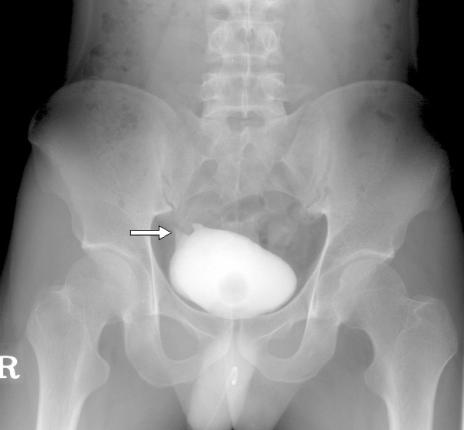

A 23-year-old man had a history of intermittent episodes of urinary tract infection with associated low abdominal pain for 15 years. Persistent bacteriuria even with prolonged antibiotics was the reason why he was referred to our hospital. Laboratory tests were normal except pyuria and growth of Escherichia coli in the urinary samples. Cystoscopy revealed a small slit-like opening on the right lateral wall of bladder dome. We found some air within the bladder and a suspicious communicating tract between the appendix and bladder on a CT scan. With a strong impression of appendicovesical fistula, a laparoscopy was performed to confirm a diagnosis and to remove the appendicovesical fistula resulting in a satisfactory result without any complication.

一名 23 岁男性,15 年来间歇性出现尿路感染,伴有下腹痛。尽管使用了长时间的抗生素治疗,但仍持续存在菌尿,这导致他被转至我院就诊。实验室检查除了尿白细胞和尿液样本中大肠埃希菌生长外,其余均正常。膀胱镜检查发现膀胱顶部右侧侧壁有一个小的裂隙样开口。我们在 CT 扫描中发现膀胱内有一些空气,以及阑尾和膀胱之间可疑的连通性。由于强烈怀疑阑尾膀胱瘘,我们进行了腹腔镜检查以明确诊断,并切除阑尾膀胱瘘,结果令人满意,无任何并发症。